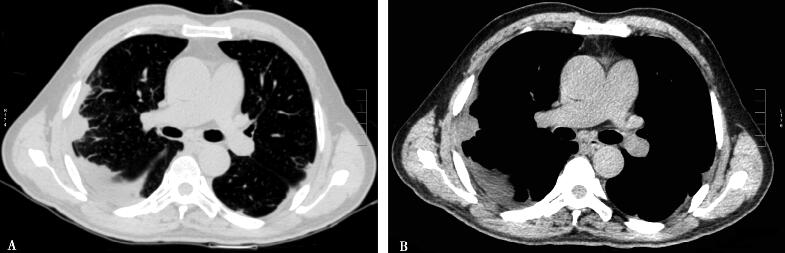

双肺多发浸润影(图1 A肺窗,B纵隔窗)。

图1

虽然血常规的检查结果仍然符合感染性疾病的特点,但较低的动脉血氧分压以及胸部影像学所见则值得推敲。患者的胸部CT显示为双肺多发浸润影,病灶分布在胸膜下,无空洞形成,伴右侧胸腔少量积液。这些表现似乎并不符合典型感染性疾病的影像学特点,同时虽然病灶的范围累及多个肺段,但似乎很难达到影响气体交换导致呼吸衰竭的程度。此时,我们对感染性疾病的最初判断产生了疑问。虽然不能完全否定感染性疾病的可能,但至少应该重新梳理我们的思路。